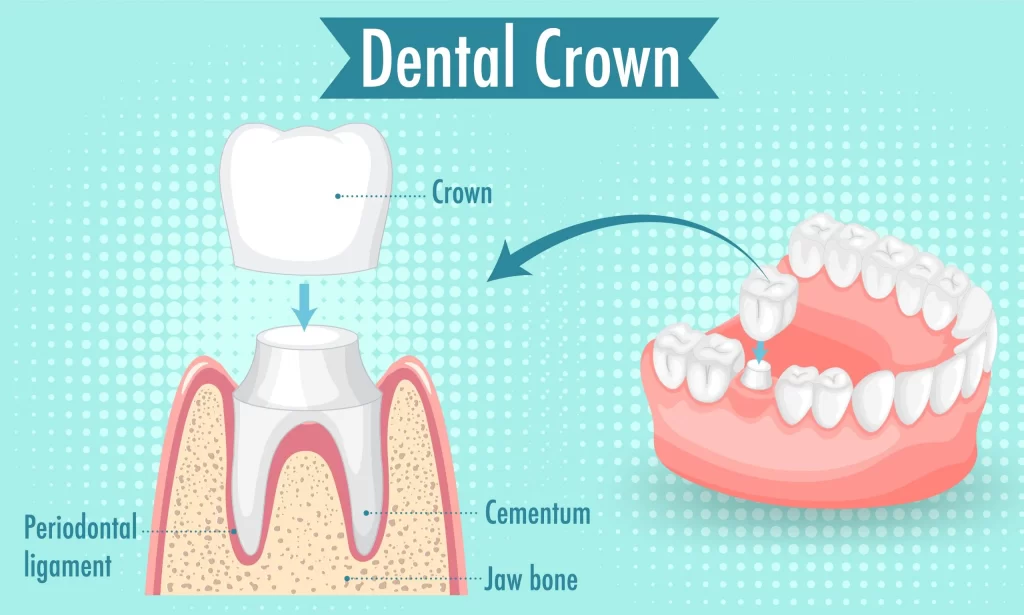

A dental crown is a cap placed over a tooth, serving to restore its shape, size, strength, and aesthetic appearance. Crowns are often recommended when a tooth is significantly decayed, fractured, or has undergone root canal treatment. They can also be used for cosmetic purposes, such as covering discolored or misshapen teeth.

- Protection of damaged teeth: Crowns can help preserve and protect weak or broken teeth.

- Cosmetic enhancement: They can enhance the appearance of a tooth that has discoloration or irregular shape.

- Support for dental bridges: Crowns are often placed on teeth adjacent to gaps to support a bridge.

- Completing root canal treatment: After the treatment, a crown provides the necessary protection to the treated tooth.

Tooth caps and dental crowns are terms that are often used interchangeably, but they have subtle differences. A tooth cap typically refers to a covering that is placed over a tooth, which is understood to have a more temporary or less extensive application than a dental crown. While dental crowns are custom-made to encase the entire tooth and are generally more robust, tooth caps might not offer the same level of protection or aesthetic enhancement.